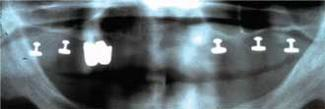

Case No. 4: The patient had a bilateral maxillary sinus graft with iliac crest bone augmented with synthetic materials. Six posterior endosteal implants, placed by the author six months after grafting, support a fixed porcelain-to-metal prosthesis. The grafting was a “refer to an experienced colleague” procedure due to the need for general anesthesia and encompassing a procedure outside of the author's clinical expertise. (Grafting done by Dr. Richard Kraut, Bronx, N.Y.) The only problem that has occurred with the case has been replacement of the prosthesis for the patient's cosmetic requirements. The case has been functioning for eight years.